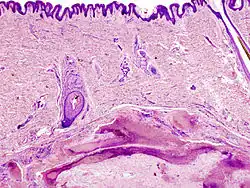

Das Pilomatrixom (Syn. Epithelioma calcificans Malherbe, Malherbe-Tumor und kalzifizierendes Epitheliom) ist ein gutartiger, palpatorisch harter Hauttumor, der insbesondere bei Kindern, aber auch in allen anderen Altersgruppen gefunden werden kann. Das Pilomatrixom leitet sich von der Haarmatrix ab. Es entsteht aus einem zystischen Gebilde, das in seinem Inneren Schattenzellen, das sind nekrotische Zellen ohne Zellkern, ausbildet und kalzifiziert (verkalkt).[1]